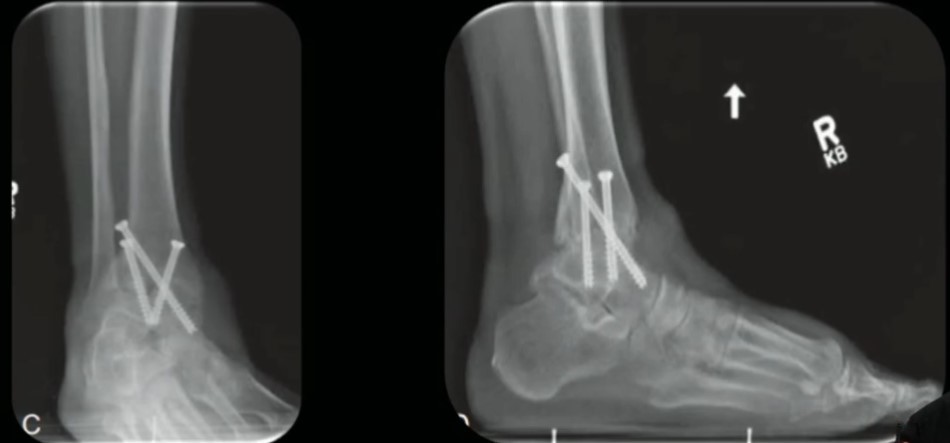

Placa

Parafusos (3: medial lateral e posterior ‘home run’)